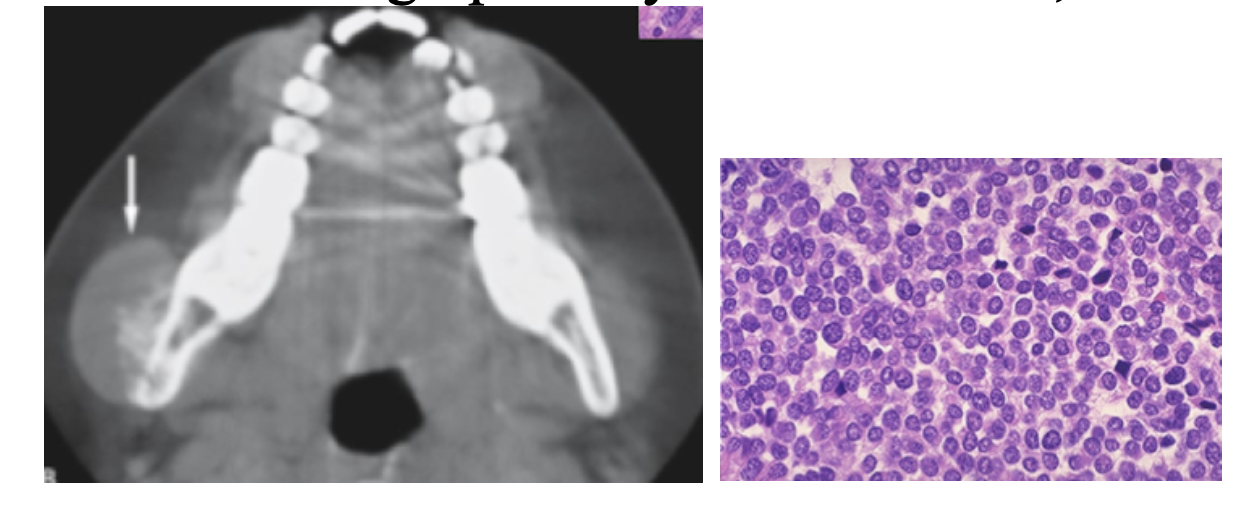

Ewing’s Sarcoma

A

Sarcoma of Long bones involving “Round cells”

Children

* rarely affects the jaw

* swelling

Moth Eaten or Onion skinning